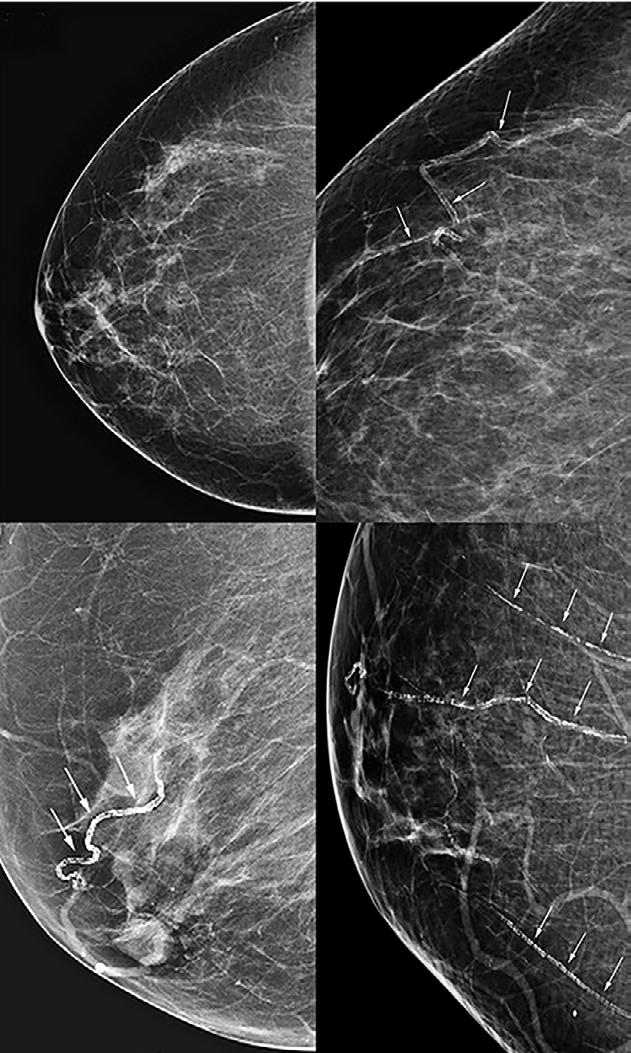

En plus d’être le meilleur moyen pour dépister le cancer du sein depuis des décennies, la mammographie peut fournir d’autres informations sur la santé des patientes, notamment sur leur santé cardio-vasculaire. Sur les quatre images de base créées lors d’une mammographie, on peut déceler des indices significatifs concernant l’état des vaisseaux sanguins et ainsi révéler une condition préoccupante. Selon la Société canadienne de l’imagerie mammaire, les problèmes cardio-vasculaires représentent la première cause de décès prématuré chez les femmes canadiennes.

Sur les clichés mammographiques, on observe parfois des éléments qui se distinguent de la graisse noire par un blanc très vif et qui arborent différentes formes. Ce sont des calcifications. La glande mammaire et la vascularisation sont d’un blanc généralement plus ténu, d’une apparence moins contrastée que les calcifications. Constituées de minéraux calciques, les calcifications ont

une densité qui se rapproche de l’os. Et si ces calcifications révélaient des informations importantes sur la santé vasculaire ? Des médecins se sont penchés sur la question en s’intéressant spécifiquement aux calcifications artérielles (figure 1 ).

L’observation de calcifications artérielles dans les seins sur les images issues de la mammographie était auparavant considérée par les radiologistes comme étant « accessoire ». Ces découvertes « fortuites » sont de plus en plus reconnues comme des informations clés concernant la santé des femmes, en particulier des femmes ménopausées. Souvent de forme oblongue, ces calcifications sont une accumulation de calcium dans la couche intermédiaire de la paroi des artères.

Bien que les radiologistes soient au courant du lien entre leur présence et le risque cardio-vasculaire, ils ne font que rarement mention de la présence de ce type de calcifications en raison de l’absence de lignes directrices pour les rapporter efficacement. Ces opacités sont des biomarqueurs de rigidité artérielle qui s’avèrent prédicateurs de maladies coronariennes.

Figure 1 : Alors que l’image de mammographie présentée en A ne montre pas de calcifications artérielles, les images B , C et D en laissent paraître plusieurs qui sont pointées par des flèches.

La Société canadienne de l’imagerie mammaire (CSBI) propose l’utilisation de cette échelle de classification qui est basée sur les calcifications artérielles visibles dans les seins (figure 2).

Figure 2 : classification des calcifications artérielles mammaires selon la CSBI :

Grade 0 : pas de calcification vasculaire.

Grade 1 : quelques calcifications vasculaires ponctuelles de petite taille, pas de calcifications en forme d’anneau ni de calcifications de forme linéaire suivant la trajectoire d’un vaisseau sanguin.

Grade 2 : calcifications vasculaires de taille moyenne ou calcifications suivant la trajectoire d’un vaisseau sanguin dans moins de trois vaisseaux sanguins

Grade 3 : calcifications vasculaires de grosse taille ou calcifications suivant la trajectoire d’un vaisseau sanguin dans au moins trois vaisseaux sanguins.